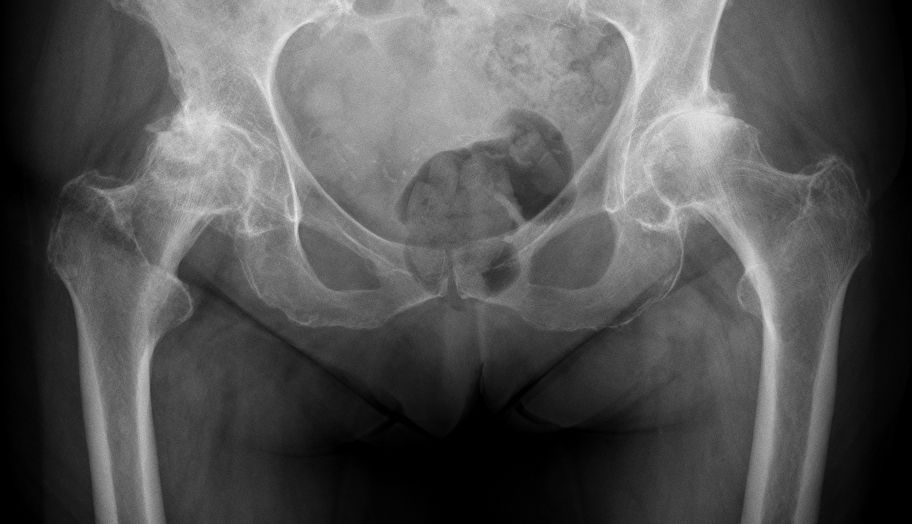

Precise biomechanical reconstruction of the hip is essential for the success of this procedure. Better clinical function and abductor strength can be achieved from optimal femoral offset and restoration of leg length. Otherwise, failure to restore the normal anatomy during THA has been associated with a higher rate of dislocation, muscle weakness, limping, leg-length discrepancy, impingement, and early loosening of the implant (Fig. 4).

To improve the accuracy of the anatomical reconstruction, there is now a greater range of implant sizes, and modular designs have been introduced to give different neck–shaft angles and stem offsets. Nevertheless, anatomical reconstruction of the hip is not always easy. To enable the surgeon to achieve this goal, different implant geometries, an increased range of implant sizes, modular implants and computer navigation systems are now available. We prefer using a fixed neck stem with three different neck angle options to better suit each patient’s specific anatomy, rather than a stem design with a single angle and two different offsets (standard/lateralized). Freed from the risk of instability, surgeons using LDH THA can then better optimize a patient's leg length and offset (Fig. 5). In our experience, a shorter leg is much better tolerated than a longer one. In the cases where the choice between a shorter or a longer head is not clear cut (example: 0mm versus +4mm), we select the shorter one.